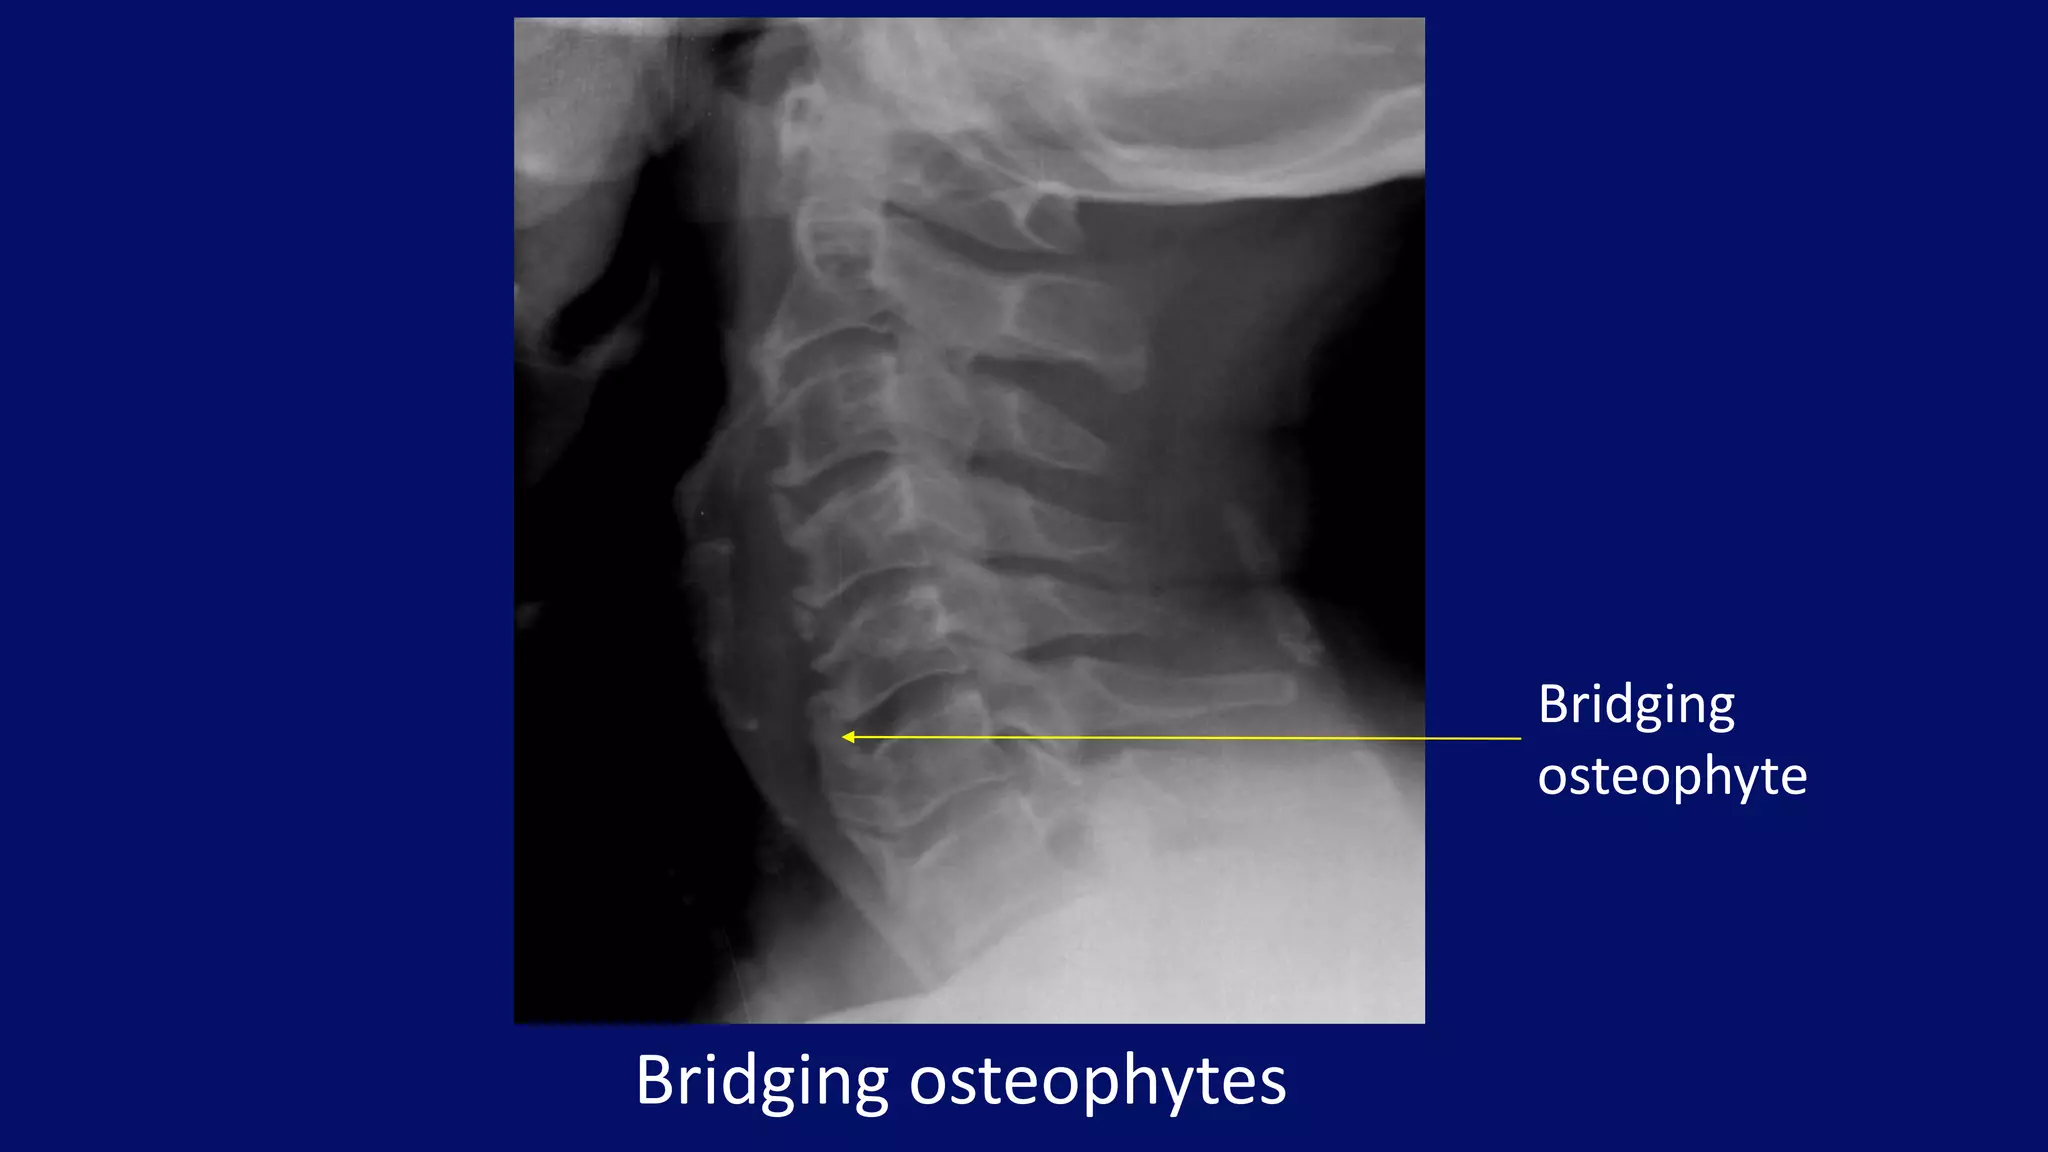

Bridging osteophytes

Bridging

osteophyte

• #39 Conventional lateral tomogram of the cervical spine in a 56-year-old man demonstrates encroachment of the neural foramina by posterior osteophytes.